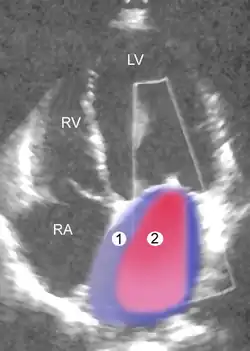

|

| Severe MR | Legend |

| 1 Left atrium (LA) – 2 MR Jet, LV Left ventricle – RV Right ventricle – RA Right atrium | |

An echocardiogram is commonly used to confirm the diagnosis of MR.[16] Color doppler flow on the transthoracic echocardiogram (TTE) will reveal a jet of blood flowing from the left ventricle into the left atrium during ventricular systole. Also, it may detect a dilated left atrium and ventricle and decreased left ventricular function.[6] A transesophageal echocardiogram can give clearer images if needed as the back of the heart can also be viewed.[17]